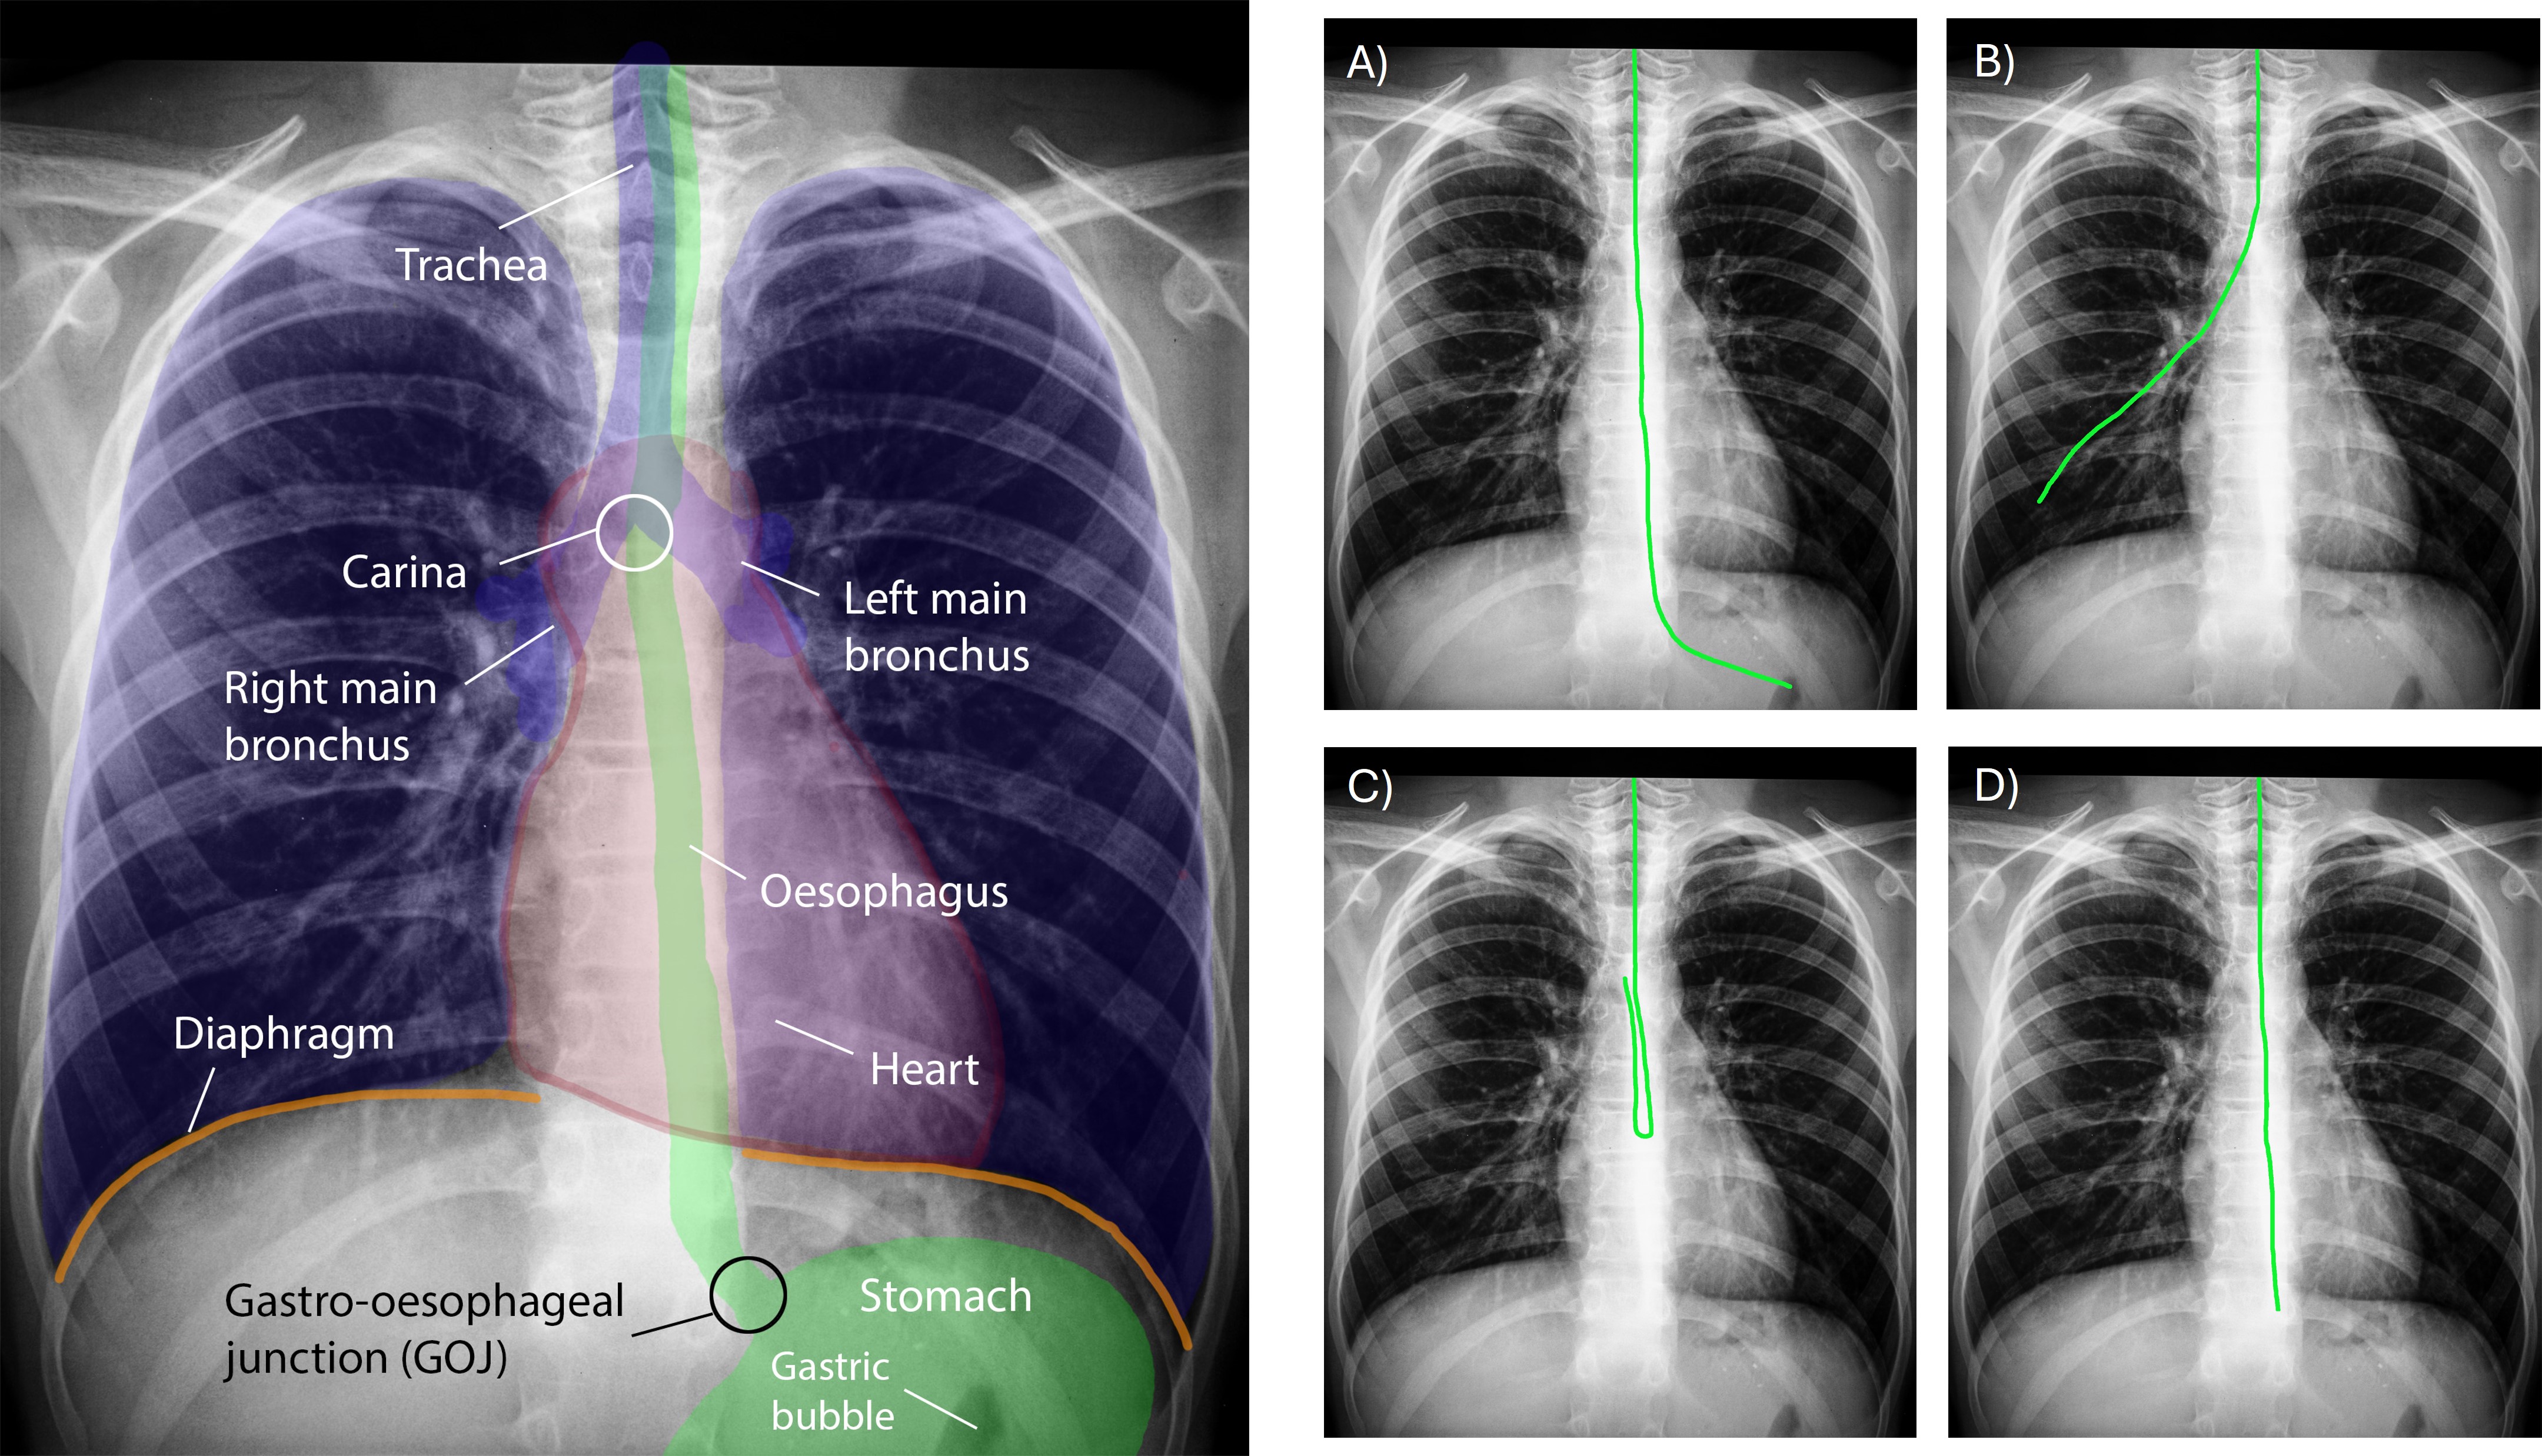

Importantly, an NGT should not be placed into the patient’s lungs. Feeding a patient through an NGT misplaced into the lungs would be a severe incident that can have critical implications – including patient death – and is classified by the UK National Health Services (NHS) as a Never Event555Never events are “serious incidents that are entirely preventable because guidance or safety recommendations providing strong systemic protective barriers are available at a national level, and should have been implemented by all healthcare providers”: https://www.england.nhs.uk/patient-safety/revised-never-events-policy-and-framework/”. Less critical, yet sub-optimally placed NGTs may not extend far enough into the stomach; need withdrawing; or may be kinked or coiled along the path – thereby inhibiting proper use and intended functionality. See Figure 3 for illustrations of normal, sub-optimal and critically (mis)placed NGTs. Any intervention to correct or replace the NGT then restarts the entire NGT verification process (Figure 1).

Refer to caption

Figure 3. Left: Simplified illustration of a patient’s key anatomical structures of relevance to NGT placement assessment (the heart is drawn for clarity only). Right: different NGT placements: A) correct placement of NGT with tip projecting in the stomach; B) critical misplacement of the NGT into the patient’s right lung (via the trachea and the right main bronchus); C) misplaced NGT which is coiled in patient’s mid oesophagus; and D) misplaced NGT with tip in distal oesophagus requiring further advancement to reach the stomach.